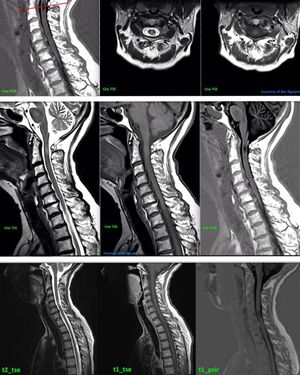

PSIR stands for Phase Sensitive Inversion Recovery and is typically used to improve the delineation of gray and white matter. In addition, the sequence provides high contrast-to-noise ratio (CNR) between MS lesions and normal tissue. TI value of PSIR sequence is selected at 350-600 ms. PSIR sequence is useful for depicting cortical grey matter lesions (common in MS), which are usually not well visible on the other series, and shows great potential in revealing MS lesions in the cervical spinal cord (figure). Images courtesy of Bac Nguyen.